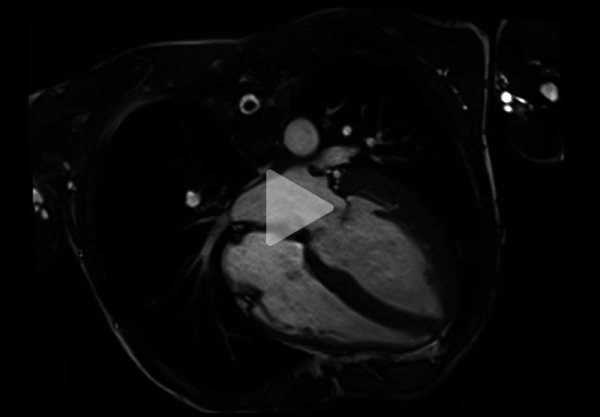

Vidéo 3 - Séquence Ciné-IRM coupe 4 cavités

Résultats de l’IRM cardiaque:

- Fonctions systoliques bi-ventriculaires conservées avec dilatation tétra-cavitaire

- HVG concentrique (masse VG à 128 g/m2 pour une normale < 90 g/m2) avec épaisseur maximale à 15 mm en antéro-septo-basal (Figure 7)

- Hypertrophie VD avec épaisseur diastolique à 5 mm (Figure 8)

- Hypertrophie des piliers mitraux (Figure 9) et trabéculations bi-ventriculaires

Aspects IRM évocateurs de maladie de Fabry :

Toute CMH, surtout si elle concentrique et si elle touche aussi le ventricule droit, doit amener à rechercher une maladie de Fabry ou une amylose cardiaque

- Toute CMH, surtout si elle concentrique et si elle touche aussi le ventricule droit, doit amener à recherche une maladie de Fabry ou une amylose cardiaque